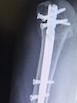

プラスボルトが5本。

プラスボルトが5本…って、

プラスボルト

かいヾ(ー ー )ォィ

※でも、

一生のお友達

v